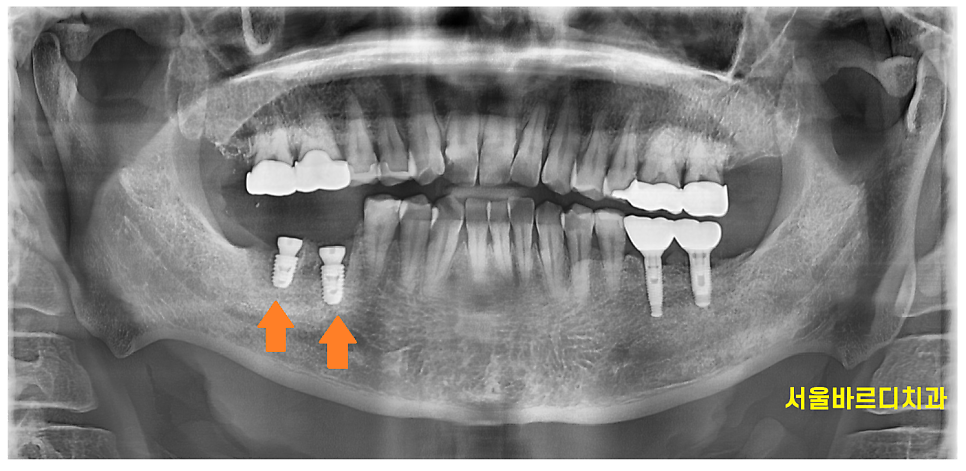

240501

신경관을 피해 안전하게 임플란트 수술 완료하였습니다.

<수술 결과>